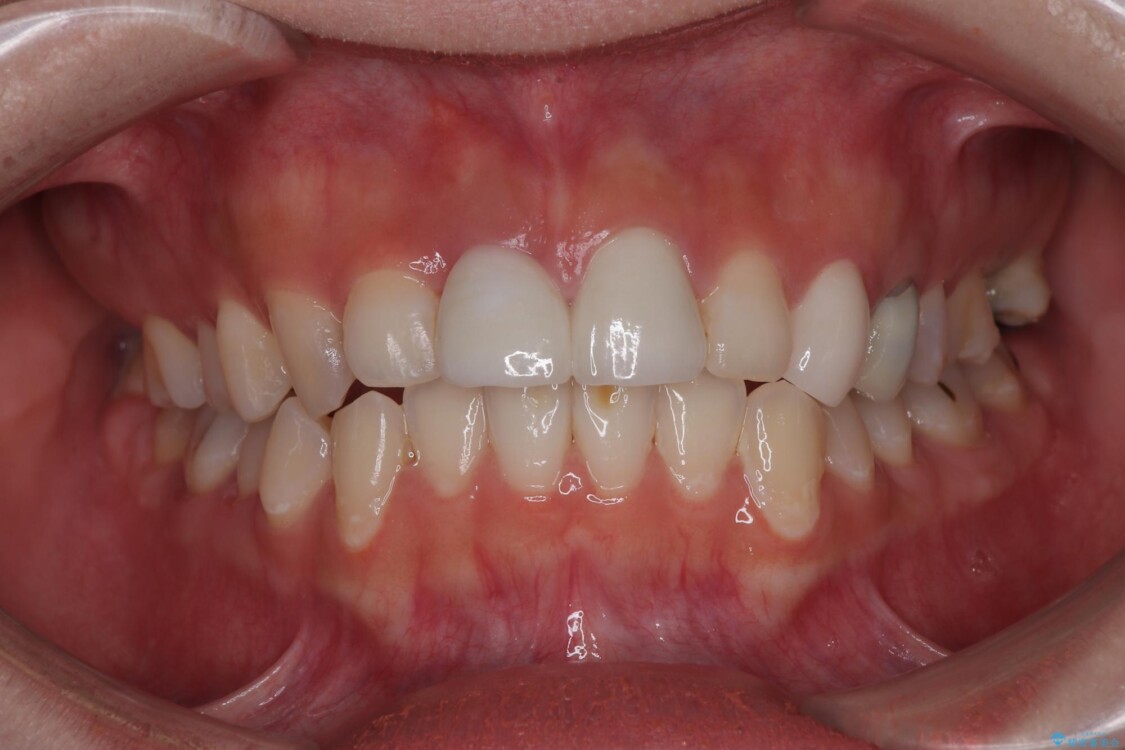

抜歯を避けられない場合でも、「即日でインプラント治療+仮歯装着」により見た目を損なわないで治療を終えることができました。

抜歯をしてインプラントを埋入してから、4か月で最終補綴物(オールセラミッククラウン)の装着まで終えることができ非常に満足いただきました。

治療後

• 「抜歯してブリッジ」と言われた20代女性が選んだ治療とは|たった4か月で自然な笑顔に抜歯即時インプラント+審美補綴の症例 治療後画像